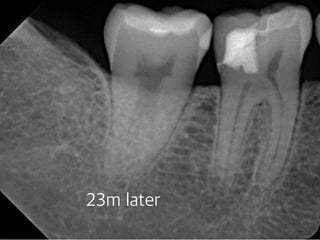

#30 Partial pulpotomy follow-upcase

(23 female)

2013 01 26 201210 13 23m later